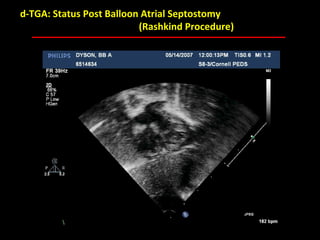

d-TGA: Status Post Balloon Atrial Septostomy

(Rashkind Procedure)

ABB MD